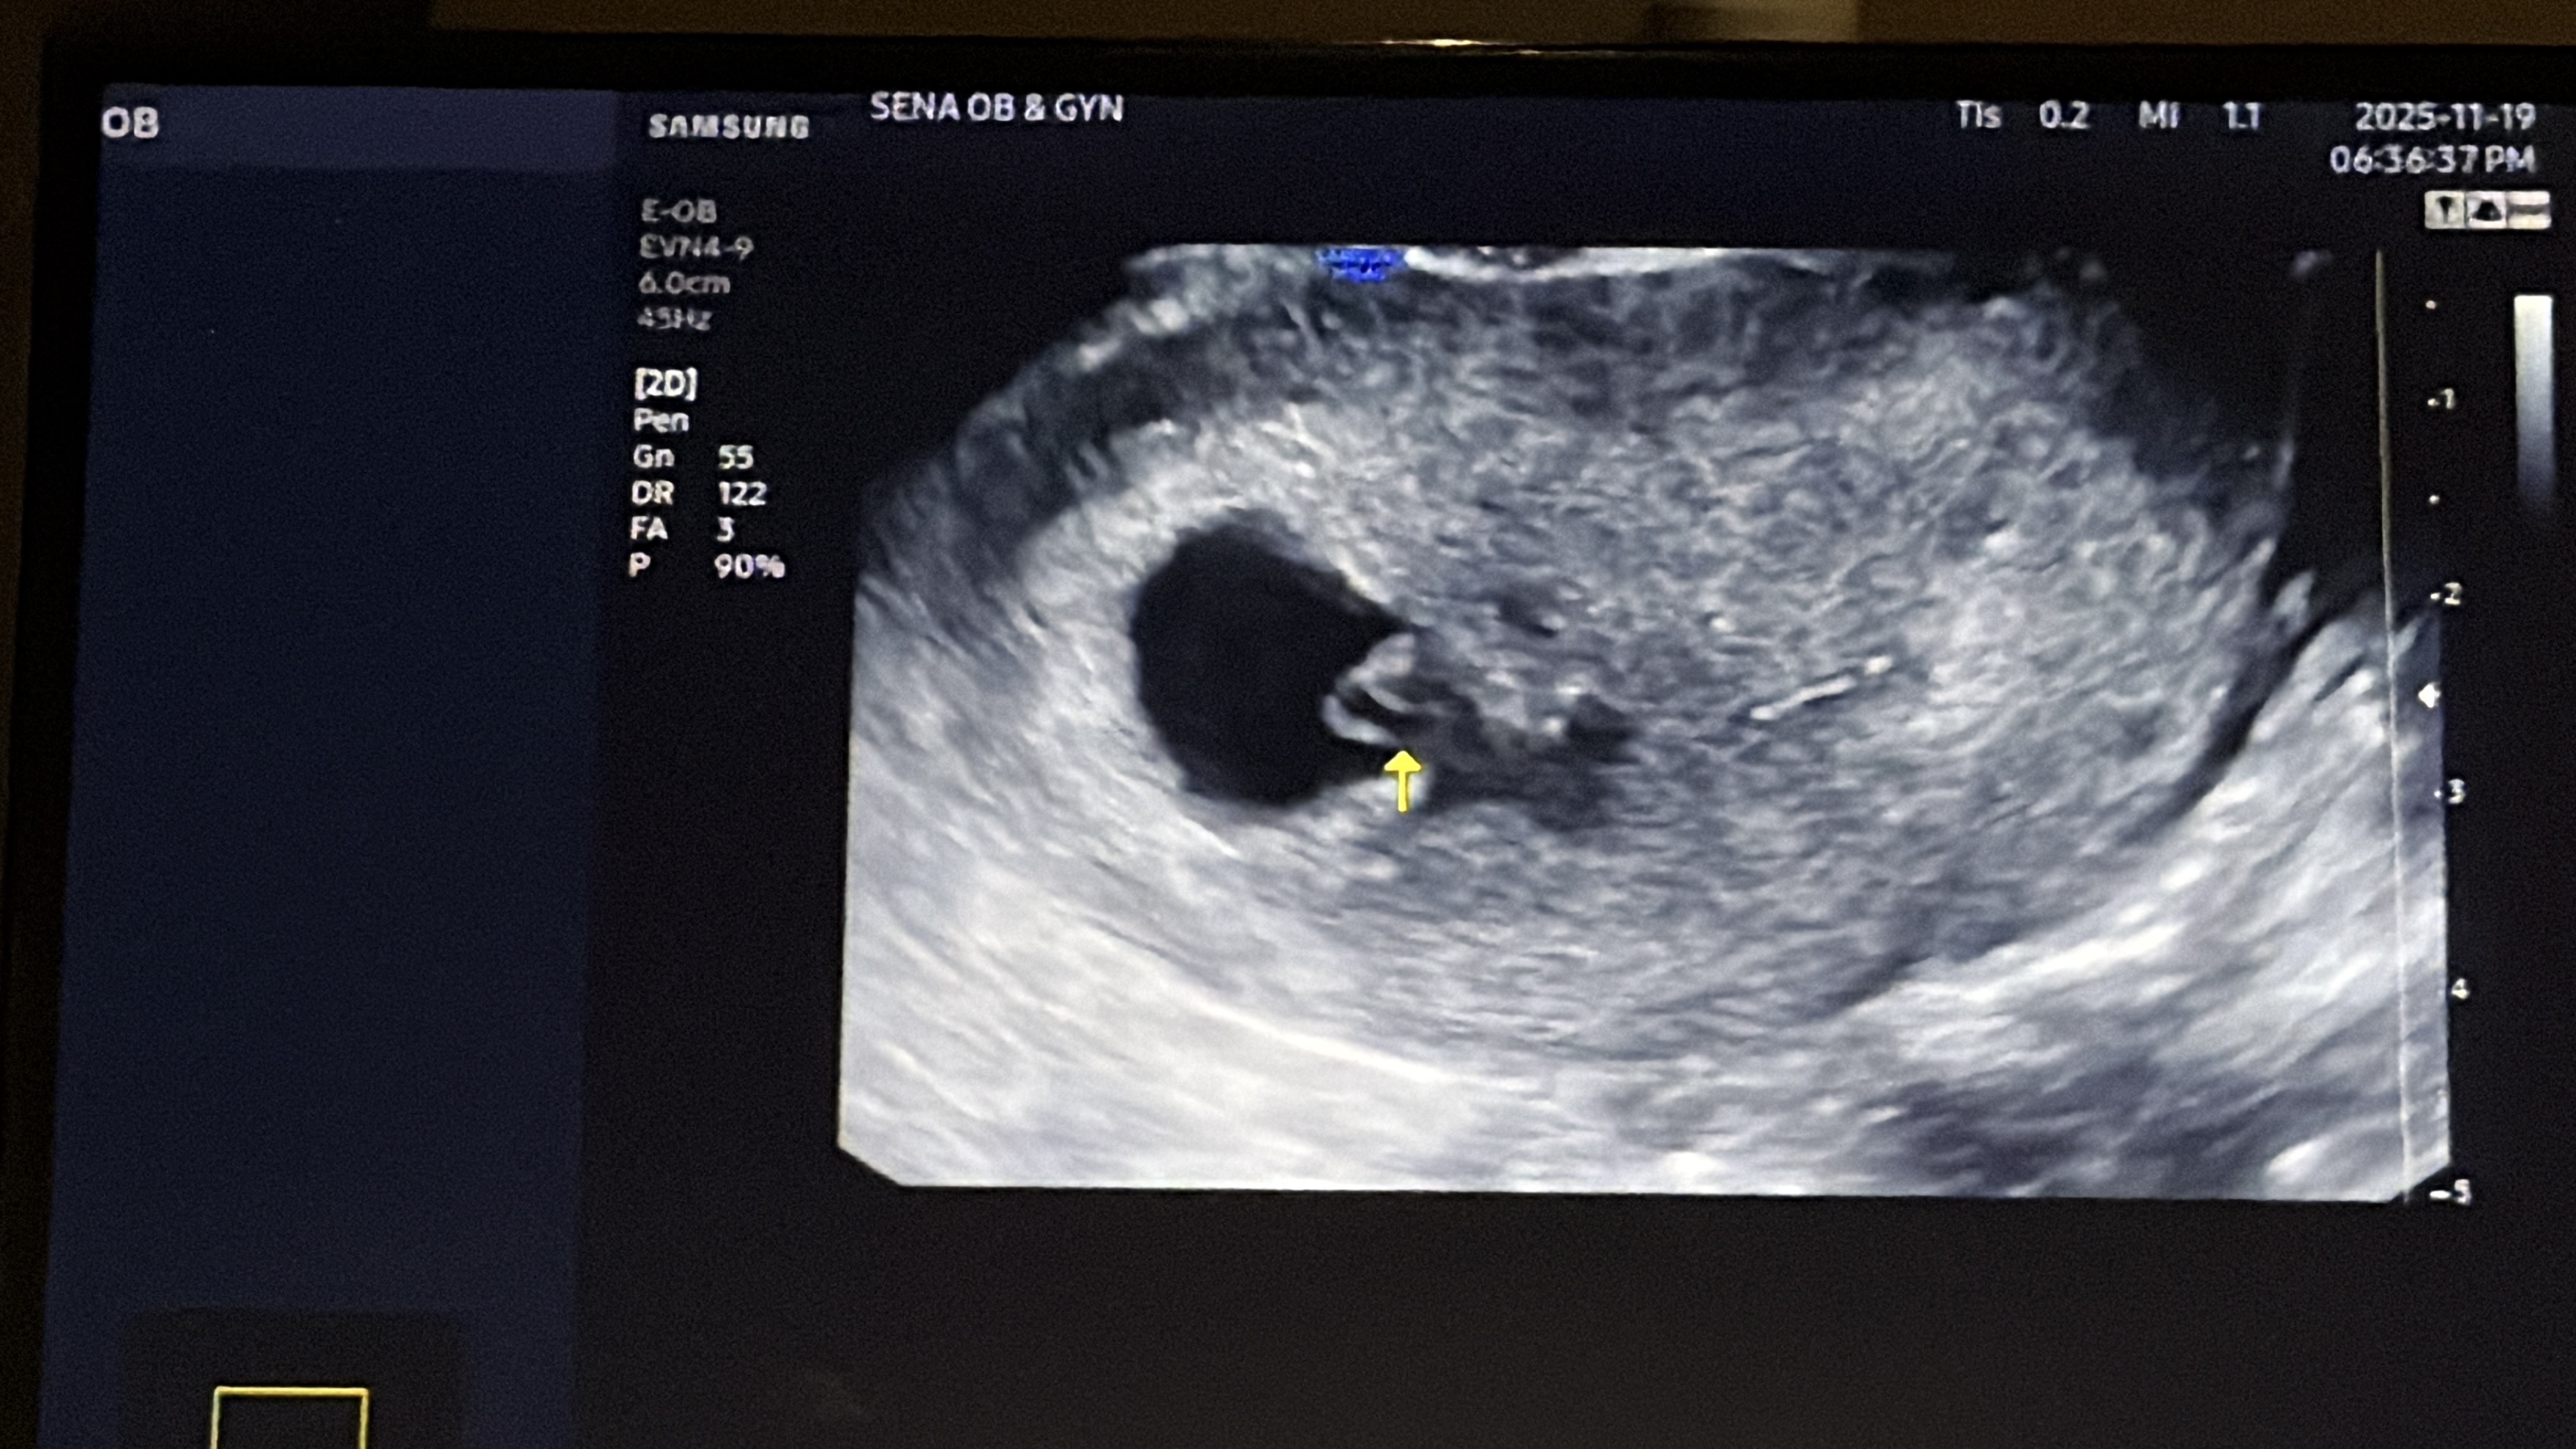

7주차인데 피고임, 주수에 비해 작음 ㅠ

심장소리 들으러 갔눈데 난황이랑 심장 잘 뛰는거 확인 후 바로 아기집 오른쪽에 피고임이 있더라구요ㅠ 아기는 주수에비해 현저히 작은데 0.37센치 피고임은 2.38센치 정도이고.. 저같은 경우의 선배산모님 없으신가오ㅠㅠ 너무 걱정되여ㅠㅠ 30%는 자연유산 가능성 있다니.. 무서워요ㅠ